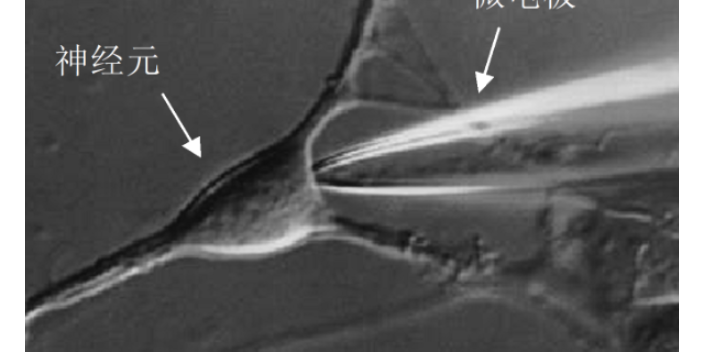

膜片鉗記錄的幾種形式:細(xì)胞吸附膜片(cell-attachedpatch)將兩次拉制后經(jīng)加熱拋光的微管電極置于清潔的細(xì)胞膜表面上,形成高阻封接,在細(xì)胞膜表面隔離出一小片膜,既而通過(guò)微管電極對(duì)膜片進(jìn)行電壓鉗制,高分辨測(cè)量膜電流,稱為細(xì)胞貼附膜片。由于不破壞細(xì)胞的完整性,這種方式又稱為細(xì)胞膜上的膜片記錄。此時(shí)跨膜電位由玻管固定電位和細(xì)胞電位決定。因此,為測(cè)定膜片兩側(cè)的電位,需測(cè)定細(xì)胞膜電位并從該電位減去玻管電位。從膜片的通道活動(dòng)看,這種形式的膜片是極穩(wěn)定的,因細(xì)胞骨架及有關(guān)代謝過(guò)程是完整的,所受的干擾小。上海醫(yī)學(xué)膜片鉗技術(shù)原理及步驟離子通道研究,膜片鉗技術(shù)供應(yīng)商上海司鼎生物,助力機(jī)理探索。

膜片鉗技術(shù)基本原理與特點(diǎn):又由于玻璃微電極管徑很小,其下膜面積光約1μm2,在這么小的面積上離子通道數(shù)量很少,一般只有一個(gè)或幾個(gè)通道,經(jīng)這一個(gè)或幾個(gè)通道流出的離子數(shù)量相對(duì)于整個(gè)細(xì)胞來(lái)講很少,可以忽略,也就是說(shuō)電極下的離子電流對(duì)整個(gè)細(xì)胞的靜息電位的影響可以忽略,那么,只要保持電極內(nèi)電位不變,則電極下的一小片細(xì)胞膜兩側(cè)的電位差就不變,從而實(shí)現(xiàn)電位固定另外,高阻封接技術(shù)還很大降低了電流記錄的背景噪聲,從而戲劇性地提高了時(shí)間、空間及電流分辨率,如時(shí)間分辨率可達(dá)10μs、空間分辨率可達(dá)1平方微米及電流分辨率可達(dá)10-12A。記錄單細(xì)胞電流和全細(xì)胞電流的基礎(chǔ)上進(jìn)一步計(jì)算出細(xì)胞膜上的通道數(shù)和開(kāi)放概率。